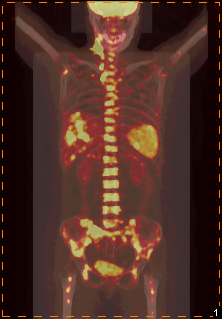

淋巴瘤

患者,女性,59岁

因“发热待查”就诊

半月来持续高热,平均体温40度

PET/CT示:

右侧颈部、双侧锁骨区、纵膈、腹膜后及右侧膈下多发淋巴结、肝及脾多发低密度灶FDG代谢异常增高;骨髓FDG代谢不均匀性异常增高

临床确诊:霍奇金淋巴瘤